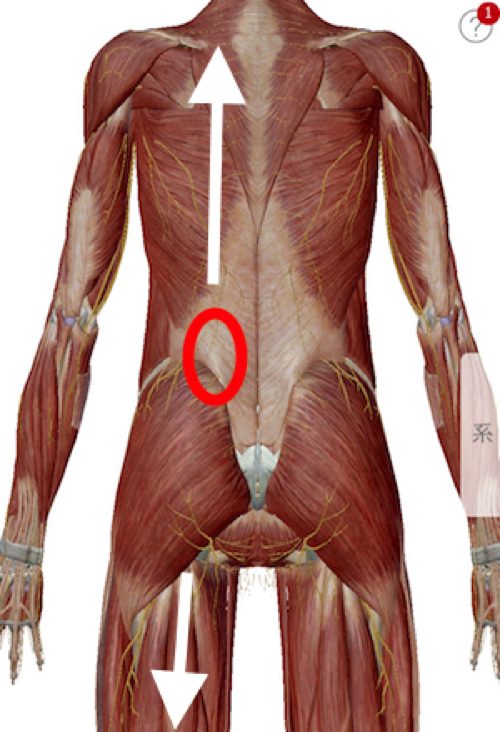

背中側を診てみると丁度こんな感じで

腰の上と下の筋肉や腱が硬直して引っ張っている状態

上下から引っ張られる状態で余裕のなくなった腰は

少し前かがみになると張り詰めてしまい激痛を生み出します。

今回のぎっくり腰で特にしっかりと施術した場所はここ